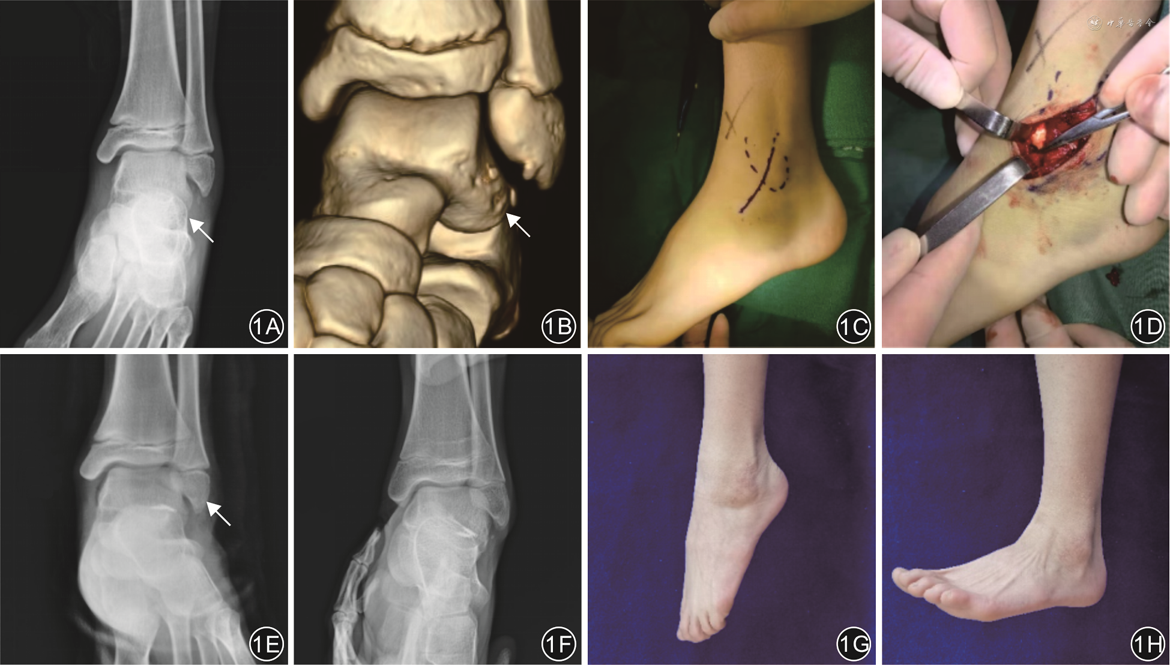

回顾性研究。纳入2017年11月—2021年4月徐州仁慈医院足踝外科4例距腓前韧带距骨侧止点撕脱骨折患者。其中,男3例,女1例;年龄15~45岁(平均30.25岁);左足2例,右足2例;运动扭伤2例,下楼扭伤1例,交通伤1例;3例患者急诊手术治疗,1例保守治疗3个月无效转手术治疗。患者术前均有外踝前下方距腓前韧带(anterior talofibular ligament,ATFL)走行区压痛,麻醉下踝关节10°跖屈位前抽屉试验阳性,均行踝关节正侧位、应力位X线片及CT检查。4例患者均采用小切口开放手术治疗距腓前韧带距骨侧损伤,手术均由同一高年资足踝外科医师完成。

患者取仰卧位,采用椎管内麻醉联合神经阻滞。患侧大腿根部固定止血带,充气加压至50 kPa。以距骨外侧撕脱骨块定位为中心,于外踝前外侧做2.5~3.0 cm弧形手术切口,依次切开皮肤、皮下组织,皮下分离时注意保护腓浅神经外侧支。沿距腓前韧带走向暴露至距骨侧止点,见距腓前韧带距骨侧止点连带部分骨皮质完全撕脱,将踝关节内翻暴露出撕脱骨折块,清理断端淤血,大量生理盐水冲洗切口。选择2枚2.8 mm金属锚钉(上海凯利台医疗科技公司,T418型)固定,定位进针点为距骨侧距腓前韧带止点处,电钻钻孔,置入金属锚定,1枚打向内上方,1枚水平位置入。术中根据距腓前韧带距骨侧止点撕脱骨折块大小,选择固定材料,缝合复位固定骨折块,将韧带缝合加强。缝合牢靠后,术中C臂X线机透视确认锚钉位置满意,检查踝关节已稳定。常规缝合,加压包扎。踝关节石膏固定于轻度外翻位。

4例患者手术均顺利完成。术后均获随访8~25个月(平均16个月)。切口均一期愈合,踝关节肿痛明显缓解,患者均未出现线结反应、感觉过敏等并发症,踝关节前抽屉实验均阴性,行走步态如常。4例患者骨折愈合良好,愈合时间3~5个月,平均3.8个月。

末次随访AOFAS踝-后足评分为89~95分(平均92.8分),Karlsson-Peterson评分为89~94分(平均91.5分)。

末次随访时ATT为(2.4±0.3)mm、TT为2.8°±0.8°,较术前的(8.4±0.8)mm、10.0°±1.4°有改善,差异均有统计学意义(t=14.40、19.62,P值均<0.001)。

近年来,关节镜下距腓前韧带修复手术治疗踝关节外侧不稳正被越来越多的临床医生认可,其手术创伤小,更容易被患者接受。与传统开放式修复相比,关节镜修复具有与其相似的临床效果,但伤口并发症发生率更低[13, 14]。在距腓前韧带修复手术中,准确识别距腓前韧带附着部位至关重要,但是关节镜手术中很难完全观察到距腓前韧带距骨侧止点。因此,对于关节镜下不能充分显露损伤部位的复杂病例,开放性修复具有明显优势。本组4例患者的距骨撕脱骨折部位在距骨外侧距腓前韧带止点处,关节镜探查及镜下缝合难度大,而且游离骨块很小,无法使用克氏针撬拨复位,镜下无法达到解剖复位;尤其是1例陈旧的撕脱骨折患者,复位前需要对骨块新鲜化处理,使骨块更易愈合。因此,本组病例更适合开放性手术治疗。

对手术时机的选择,冯仕明等[17]利用踝关节镜对距腓前韧带损伤患者早期进行修复,术后结果良好。本研究中有3例患者急诊入院手术治疗,通过早期开放修复距腓前韧带在距骨侧的撕脱骨折,术后随访过程中患者疼痛明显缓解,踝关节运动水平恢复正常,骨折愈合时间3~4个月(平均3.33个月)。本组中有1例陈旧损伤患者伤后3个月来院,术中见骨折端增生硬化,清理骨折断端硬化骨至出血,使其表面新鲜化再行复位,患者的后期愈合良好,愈合时间约5个月,较其余3例新鲜骨折的患者稍长;但是1例陈旧性损伤病例不具代表性,对于手术时机的选择还需要大量的病例研究来论证。

本组4例患者均采用踝关节前外侧小切口结合置入锚钉的方式修复距腓前韧带在距骨侧止点的损伤,切口小、暴露充分,利于手术操作,术中直视下解剖复位撕脱的距骨骨块并修复受损韧带,同时避免了损伤腓浅神经。术后4例患者的踝部切口均一期愈合,无皮肤软组织感染、线结反应等并发症,早期行功能锻炼,踝关节活动度恢复基本正常,前抽屉实验阴性,行走步态如常;末次随访AOFAS踝-后足评分及Karlsson-Peterson评分均显示疗效满意,ATT和TT较术前改善。